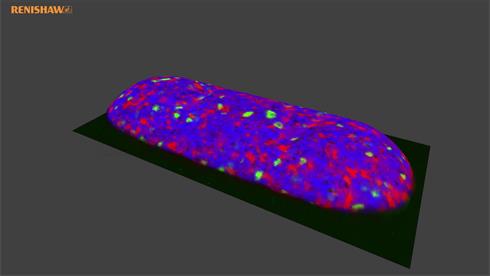

- Generate images of the formulations used in tablets, inhalers and nasal sprays at sub-micrometre spatial resolution

Rapidly generate images of your formulations with StreamLine™. This uses line focus illumination, allowing you to use higher laser powers without risk of sample damage, thereby reducing experiment times.

With the RA802 pharmaceutical analyser you can achieve imaging speeds of over 1500 spectra/s. It takes less than 2 minutes, from placing a standard tablet in the system, to generate a full, high resolution Raman image.

Generate images of formulations

Ensure your chemical images are representative; use Renishaw's StreamLine. You can change resolution to suit your domain size and, because Renishaw's WiRE software can cope with massive data files, you can analyse over the entire sample surface. Powerful Renishaw features, such as Slalom (to ensure the whole surface is sampled) and HD imaging (to get crisp clear images), provide all the options you need, whatever your formulation.